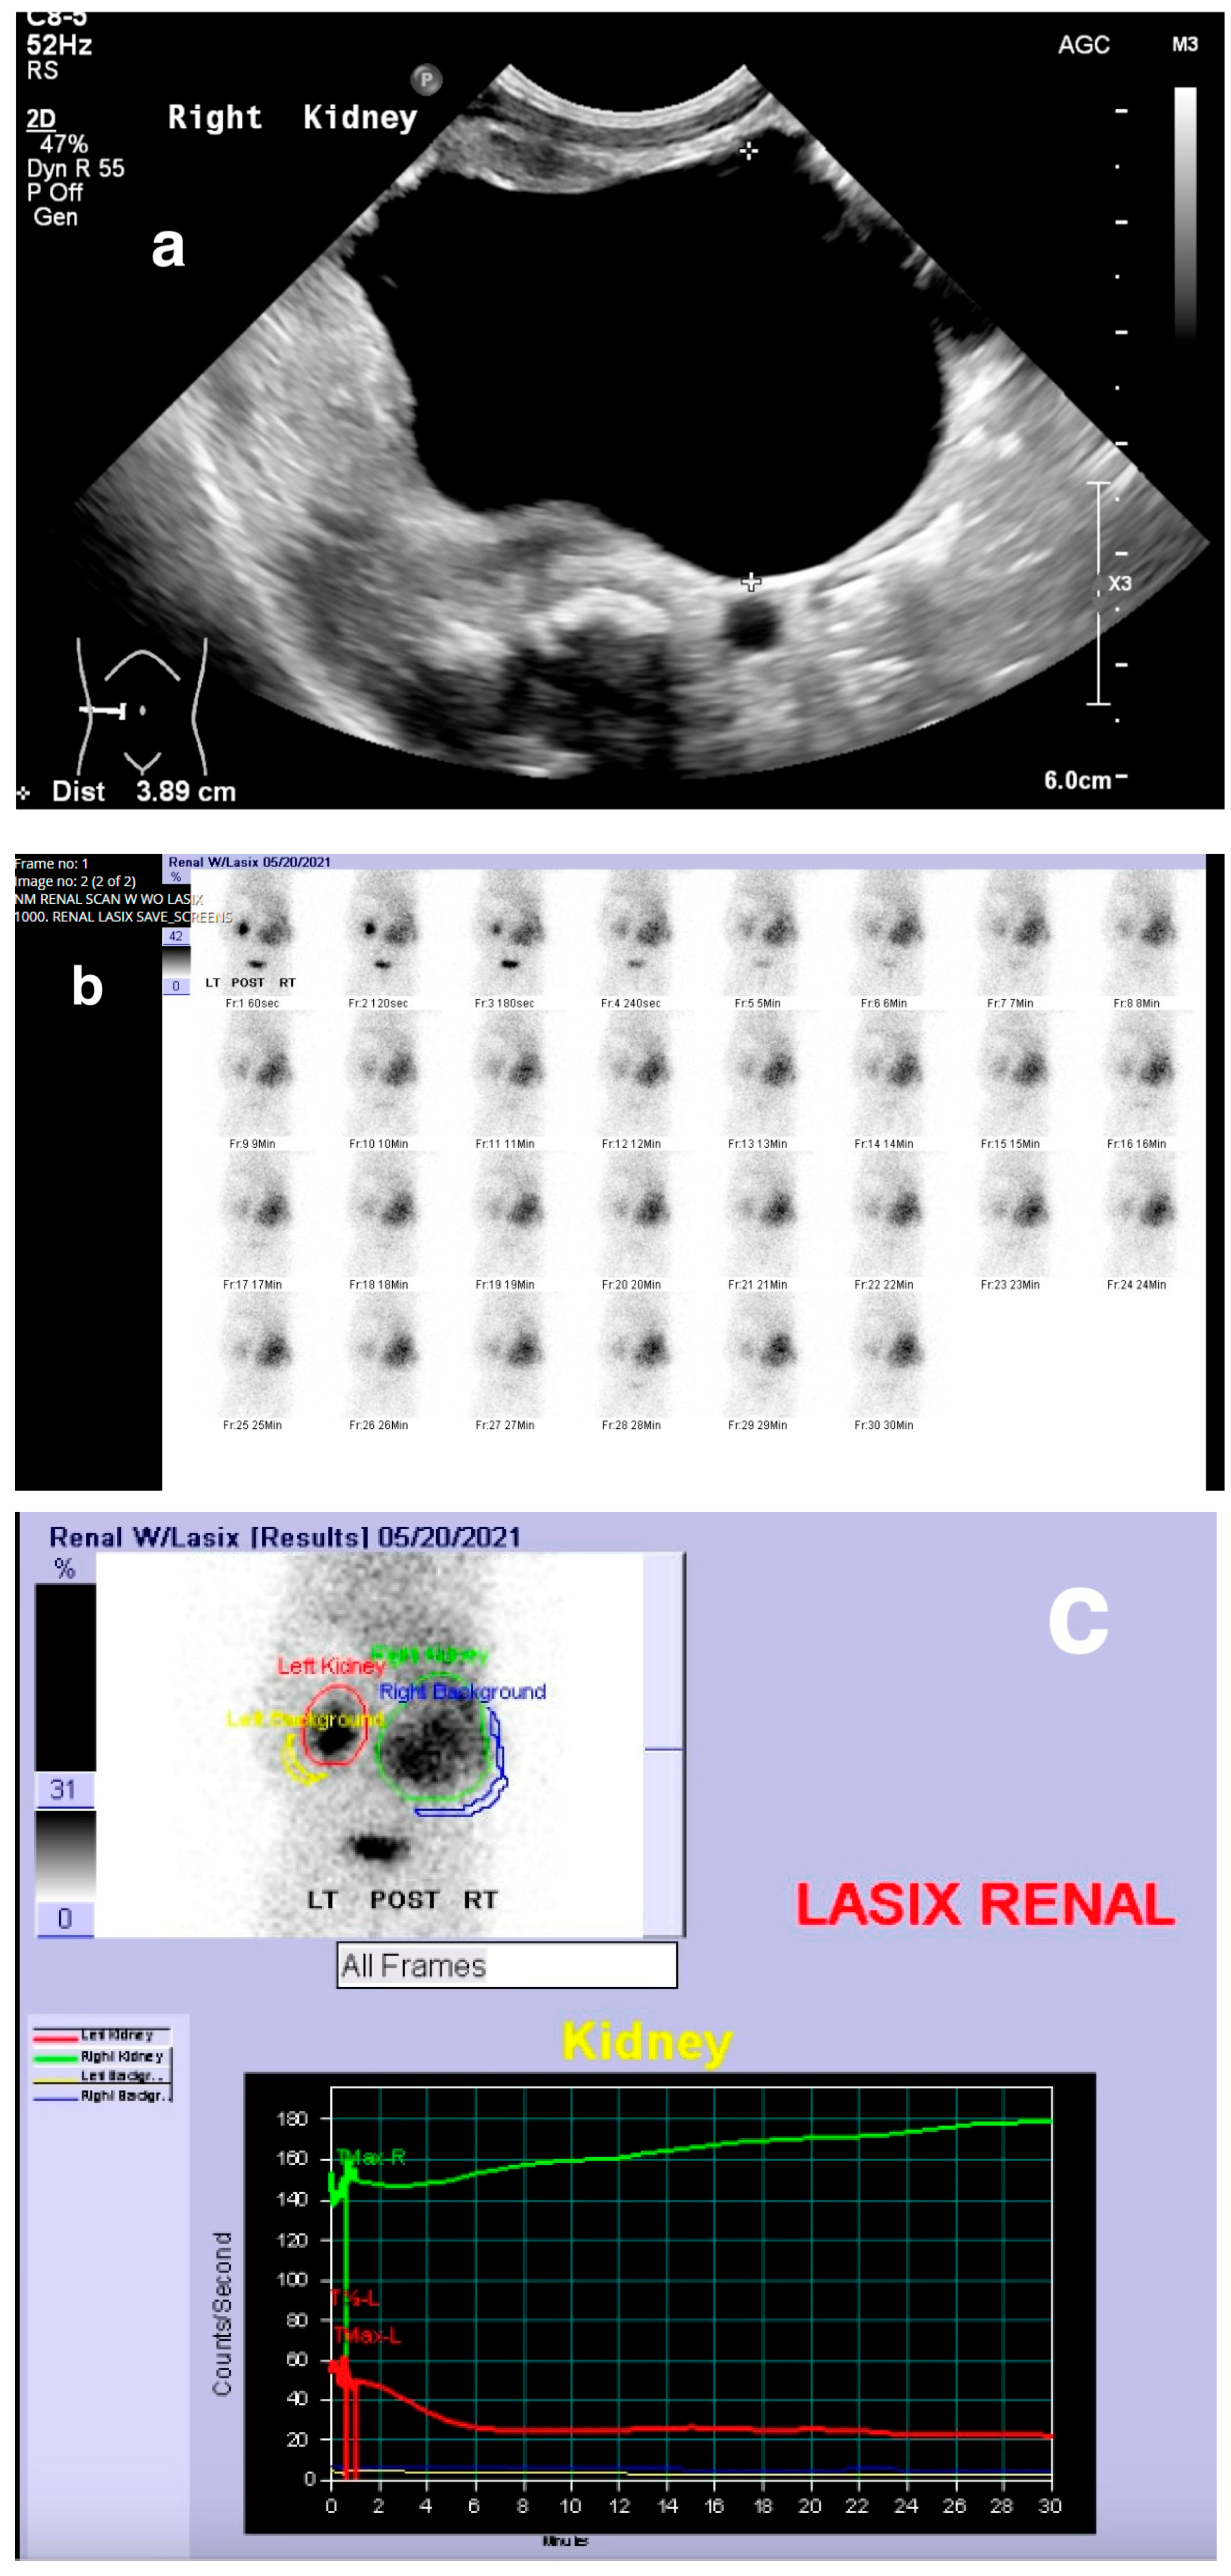

8.1.2. Dynamic Renal Scintigraphy

13. Obstructive Uropathy

- Jacobson, D.L.; Flink, C.C.; Johnson, E.K.; Maizels, M.; Yerkes, E.B.; Lindgren, B.W.; Liu, D.B.; Rosoklija, I.; Cheng, E.Y.; Gong, E.M. The Correlation between Serial Ultrasound and Diuretic Renography in Children with Severe Unilateral Hydronephrosis. J. Urol. 2018, 200, 440–446. [Google Scholar] [CrossRef] [PubMed]

- Kandur, Y.; Salan, A.; Guler, A.G.; Tuten, F. Diuretic renography in hydronephrosis: A retrospective single-center study. Int. Urol. Nephrol. 2018, 50, 1199–1204. [Google Scholar] [CrossRef] [PubMed]